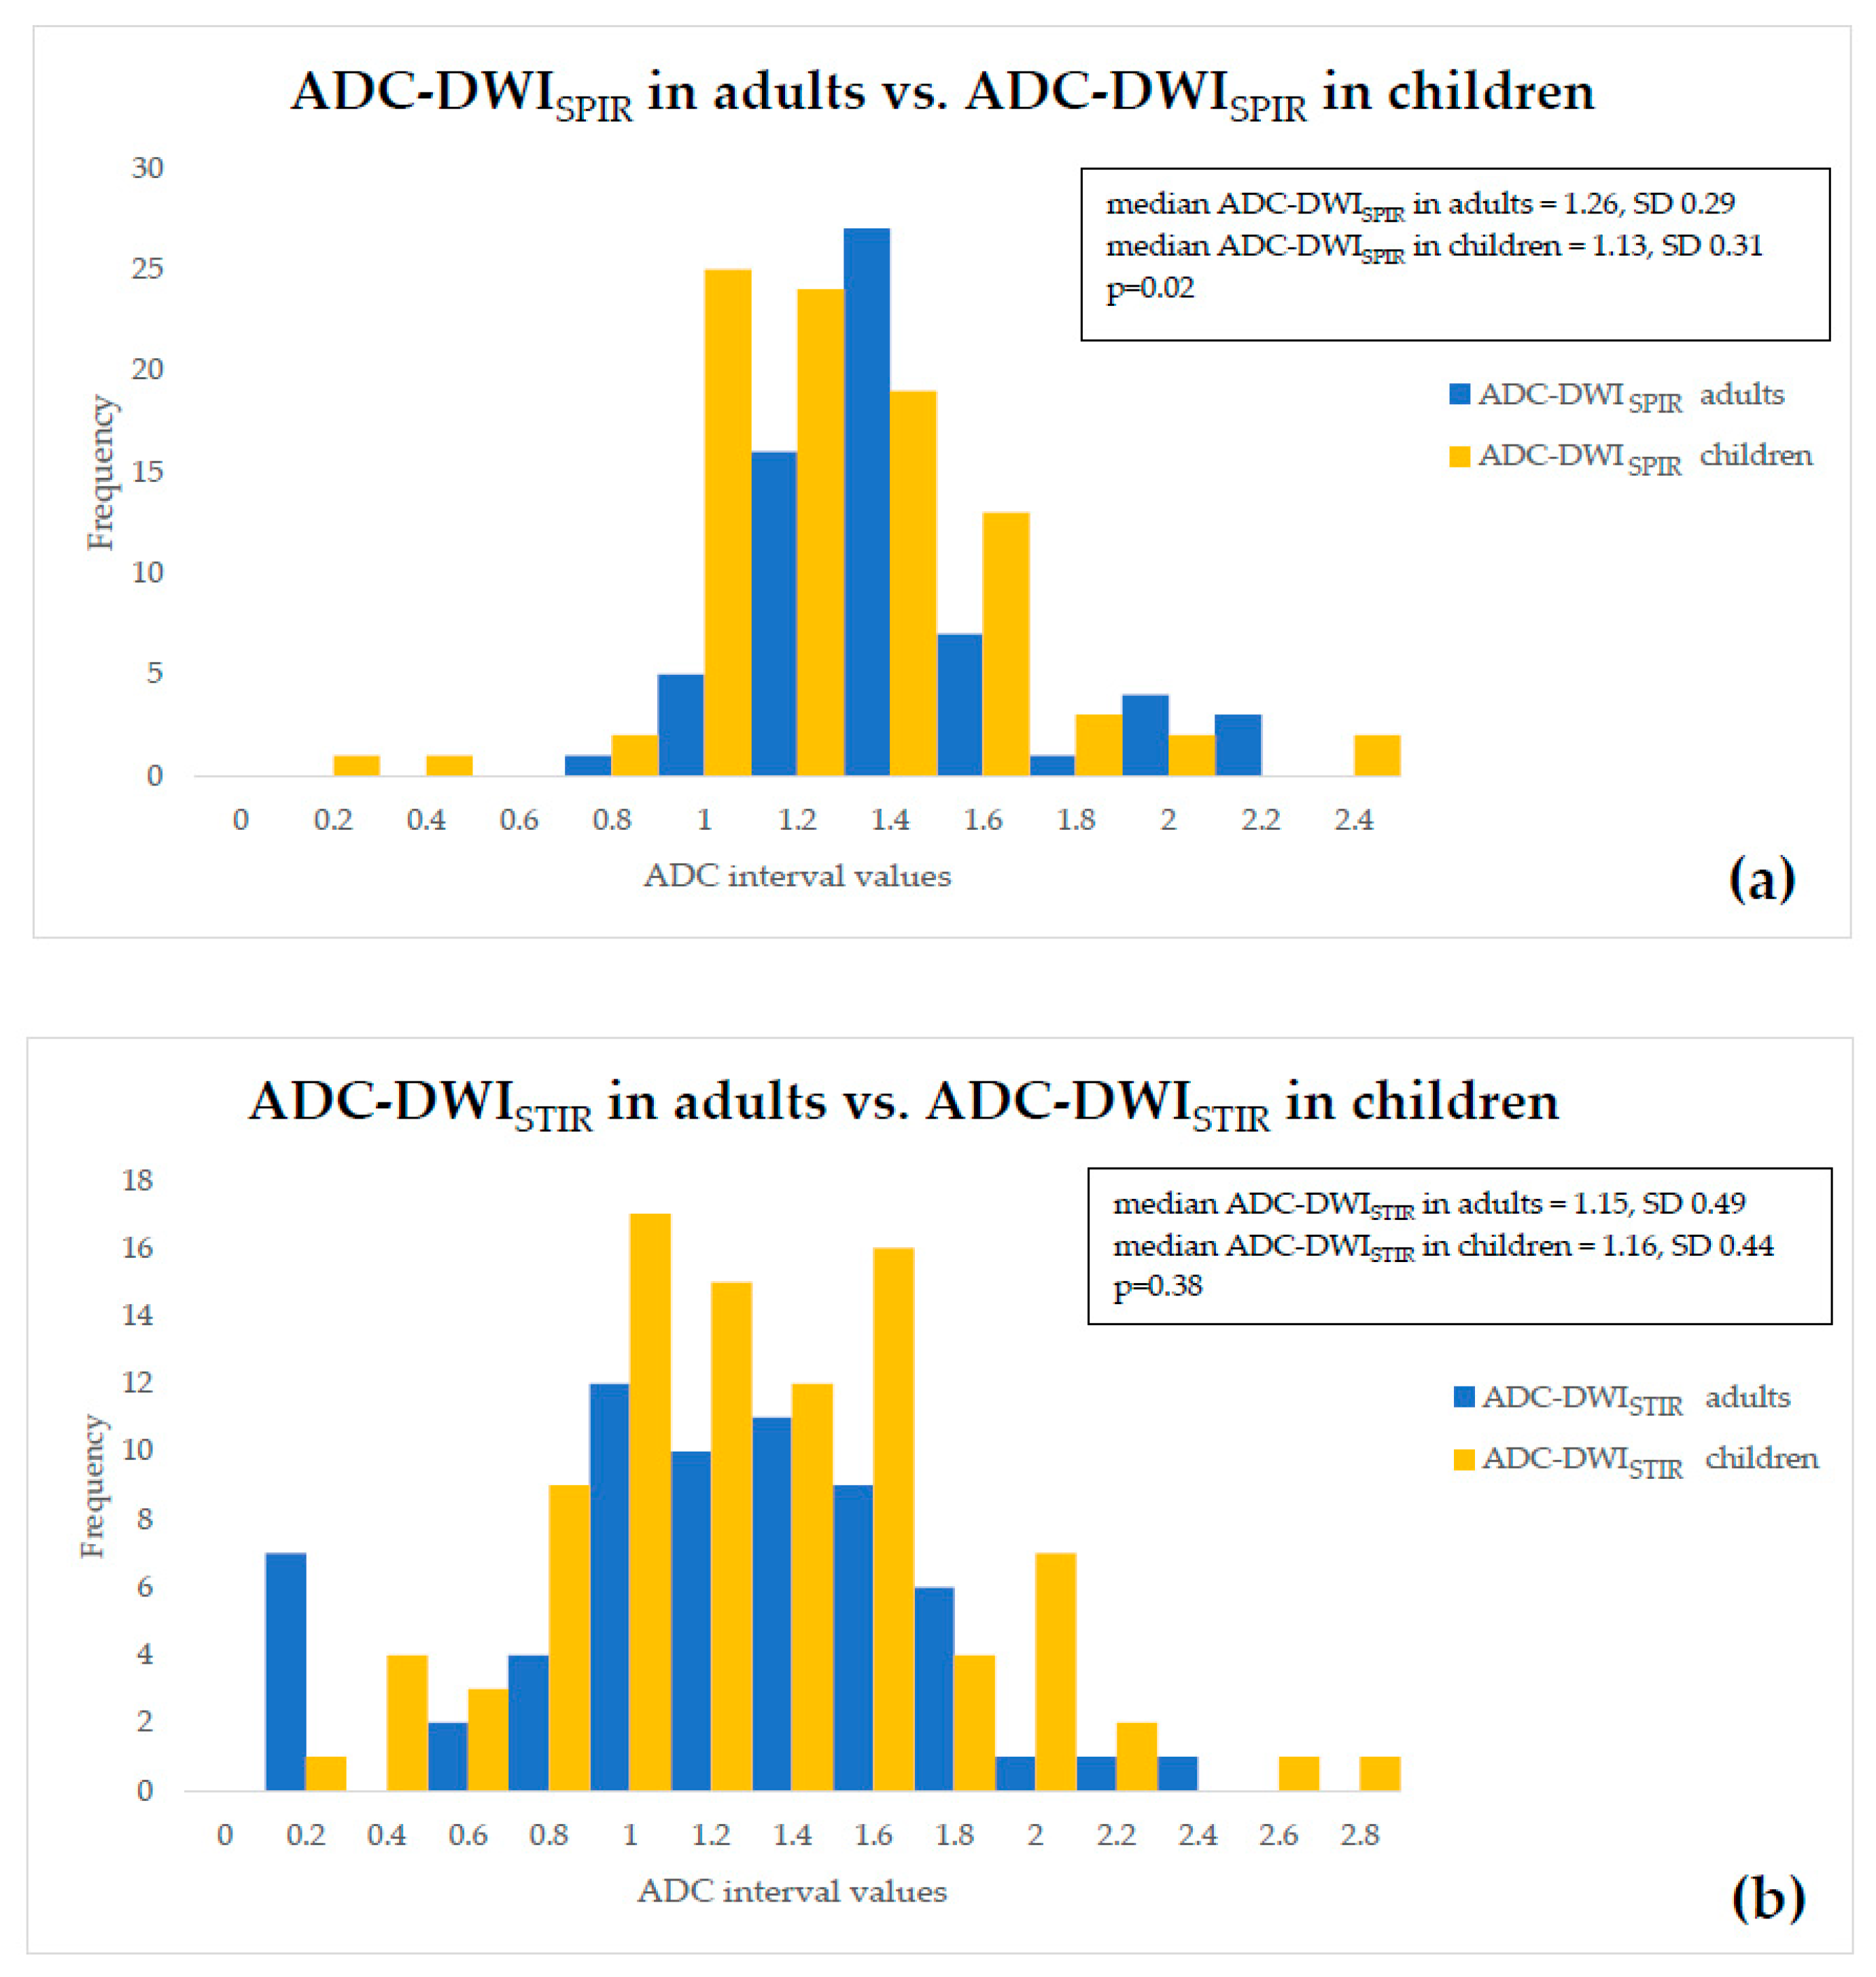

- ADC values of both adults and children were compared within a single fat suppression technique, and we observed statistically significant ADC-DWISPIR difference between adults and children (1.31 × 10−3 mm2/s, SD 0.29, vs. 1.16 × 10−3 mm2/s, SD 0.31; p = 0.02), with 12.12% lower ADC values in children compared to adults, but no statistically significant difference between the ADC-DWISTIR values in adults and children (1.09 × 10−3 mm2/s, SD 0.49, vs. 1.20 mm2/s × 10−3, SD 0.44; p = 0.38);